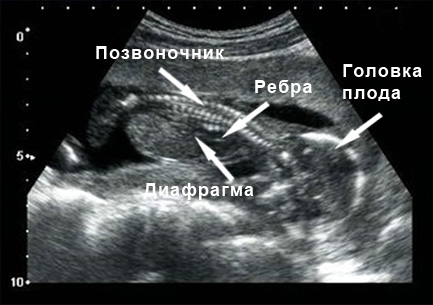

Ультразвуковое исследование на 16 неделе беременности

На данном этапе беременности ультразвуковое исследование, как правило, не проводится. Оно может быть назначено только при наличии определенных медицинских показаний, например, если результаты других анализов вызывают сомнения или если у женщины есть жалобы. К примеру, если беременная испытывает тянущую боль в области поясницы, УЗИ может помочь оценить тонус матки. Однако стоит отметить, что ультразвуковое исследование не дает полной картины, а используется лишь для подтверждения или опровержения предположений врача.

Во время ультразвукового исследования специалист анализирует структуру плаценты, ее размеры и положение, а также проводит фетометрию — измерение размеров плода. Эта процедура позволяет оценить правильность развития ребенка и выявить ранние формы задержки внутриутробного развития (ЗВУР).

На этом сроке беременности уже существует высокая вероятность определения пола ребенка, если половые органы малыша четко видны на экране. Кроме того, можно попросить специалиста сделать снимок во время исследования, чтобы сохранить воспоминания о том, как выглядел ваш малыш на 16-й неделе беременности.

Фото УЗИ на 16 неделе беременности

На нашем сайте вы найдете УЗИ по неделям беременности с фотографиями.